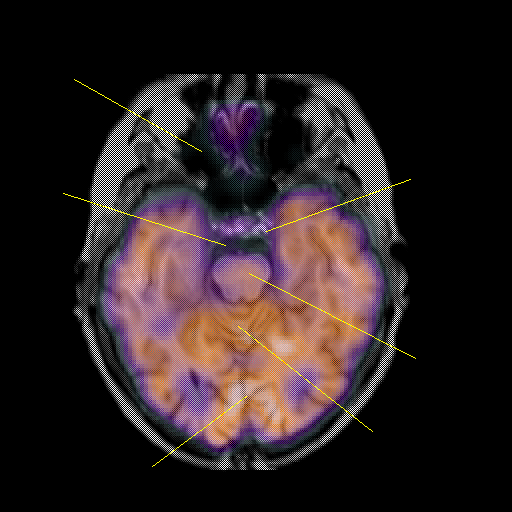

overlay: Slice 19

Slice 19

MRCBFCBF with

Unlabeled

Pointers

Labeled